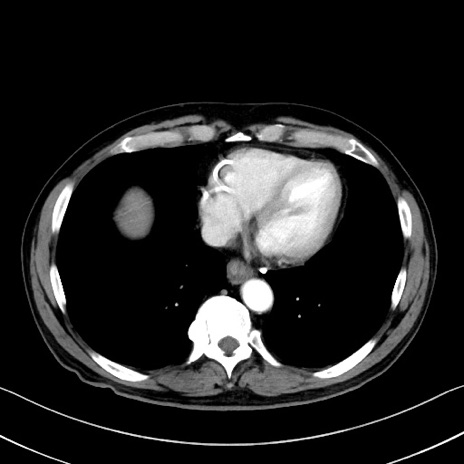

症例35(横断像)

【症例】70歳代 男性

【主訴】腹部膨満、嘔吐

【現病歴】昨日より腹部膨満感出現。本日増悪し、仙痛出現。嘔吐あり、受診。

【既往歴】糖尿病、胆摘後

【身体所見】BP 149/80mmHg、HR 74/min、BT 35.9℃、腹部:膨満、軟、圧痛なし。腸雑音減弱あり。上腹部正中切開瘢痕あり。

【データ】WBC 13500、CRP 1.72